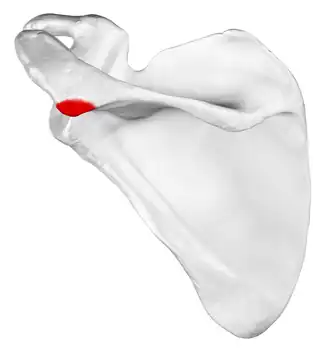

Left scapula. Posterior view. Acromional angle shown in red. | |

Acromial angle is a prominent bony point at the junction of the lateral border of acromion and the spine of scapula.[1][2]